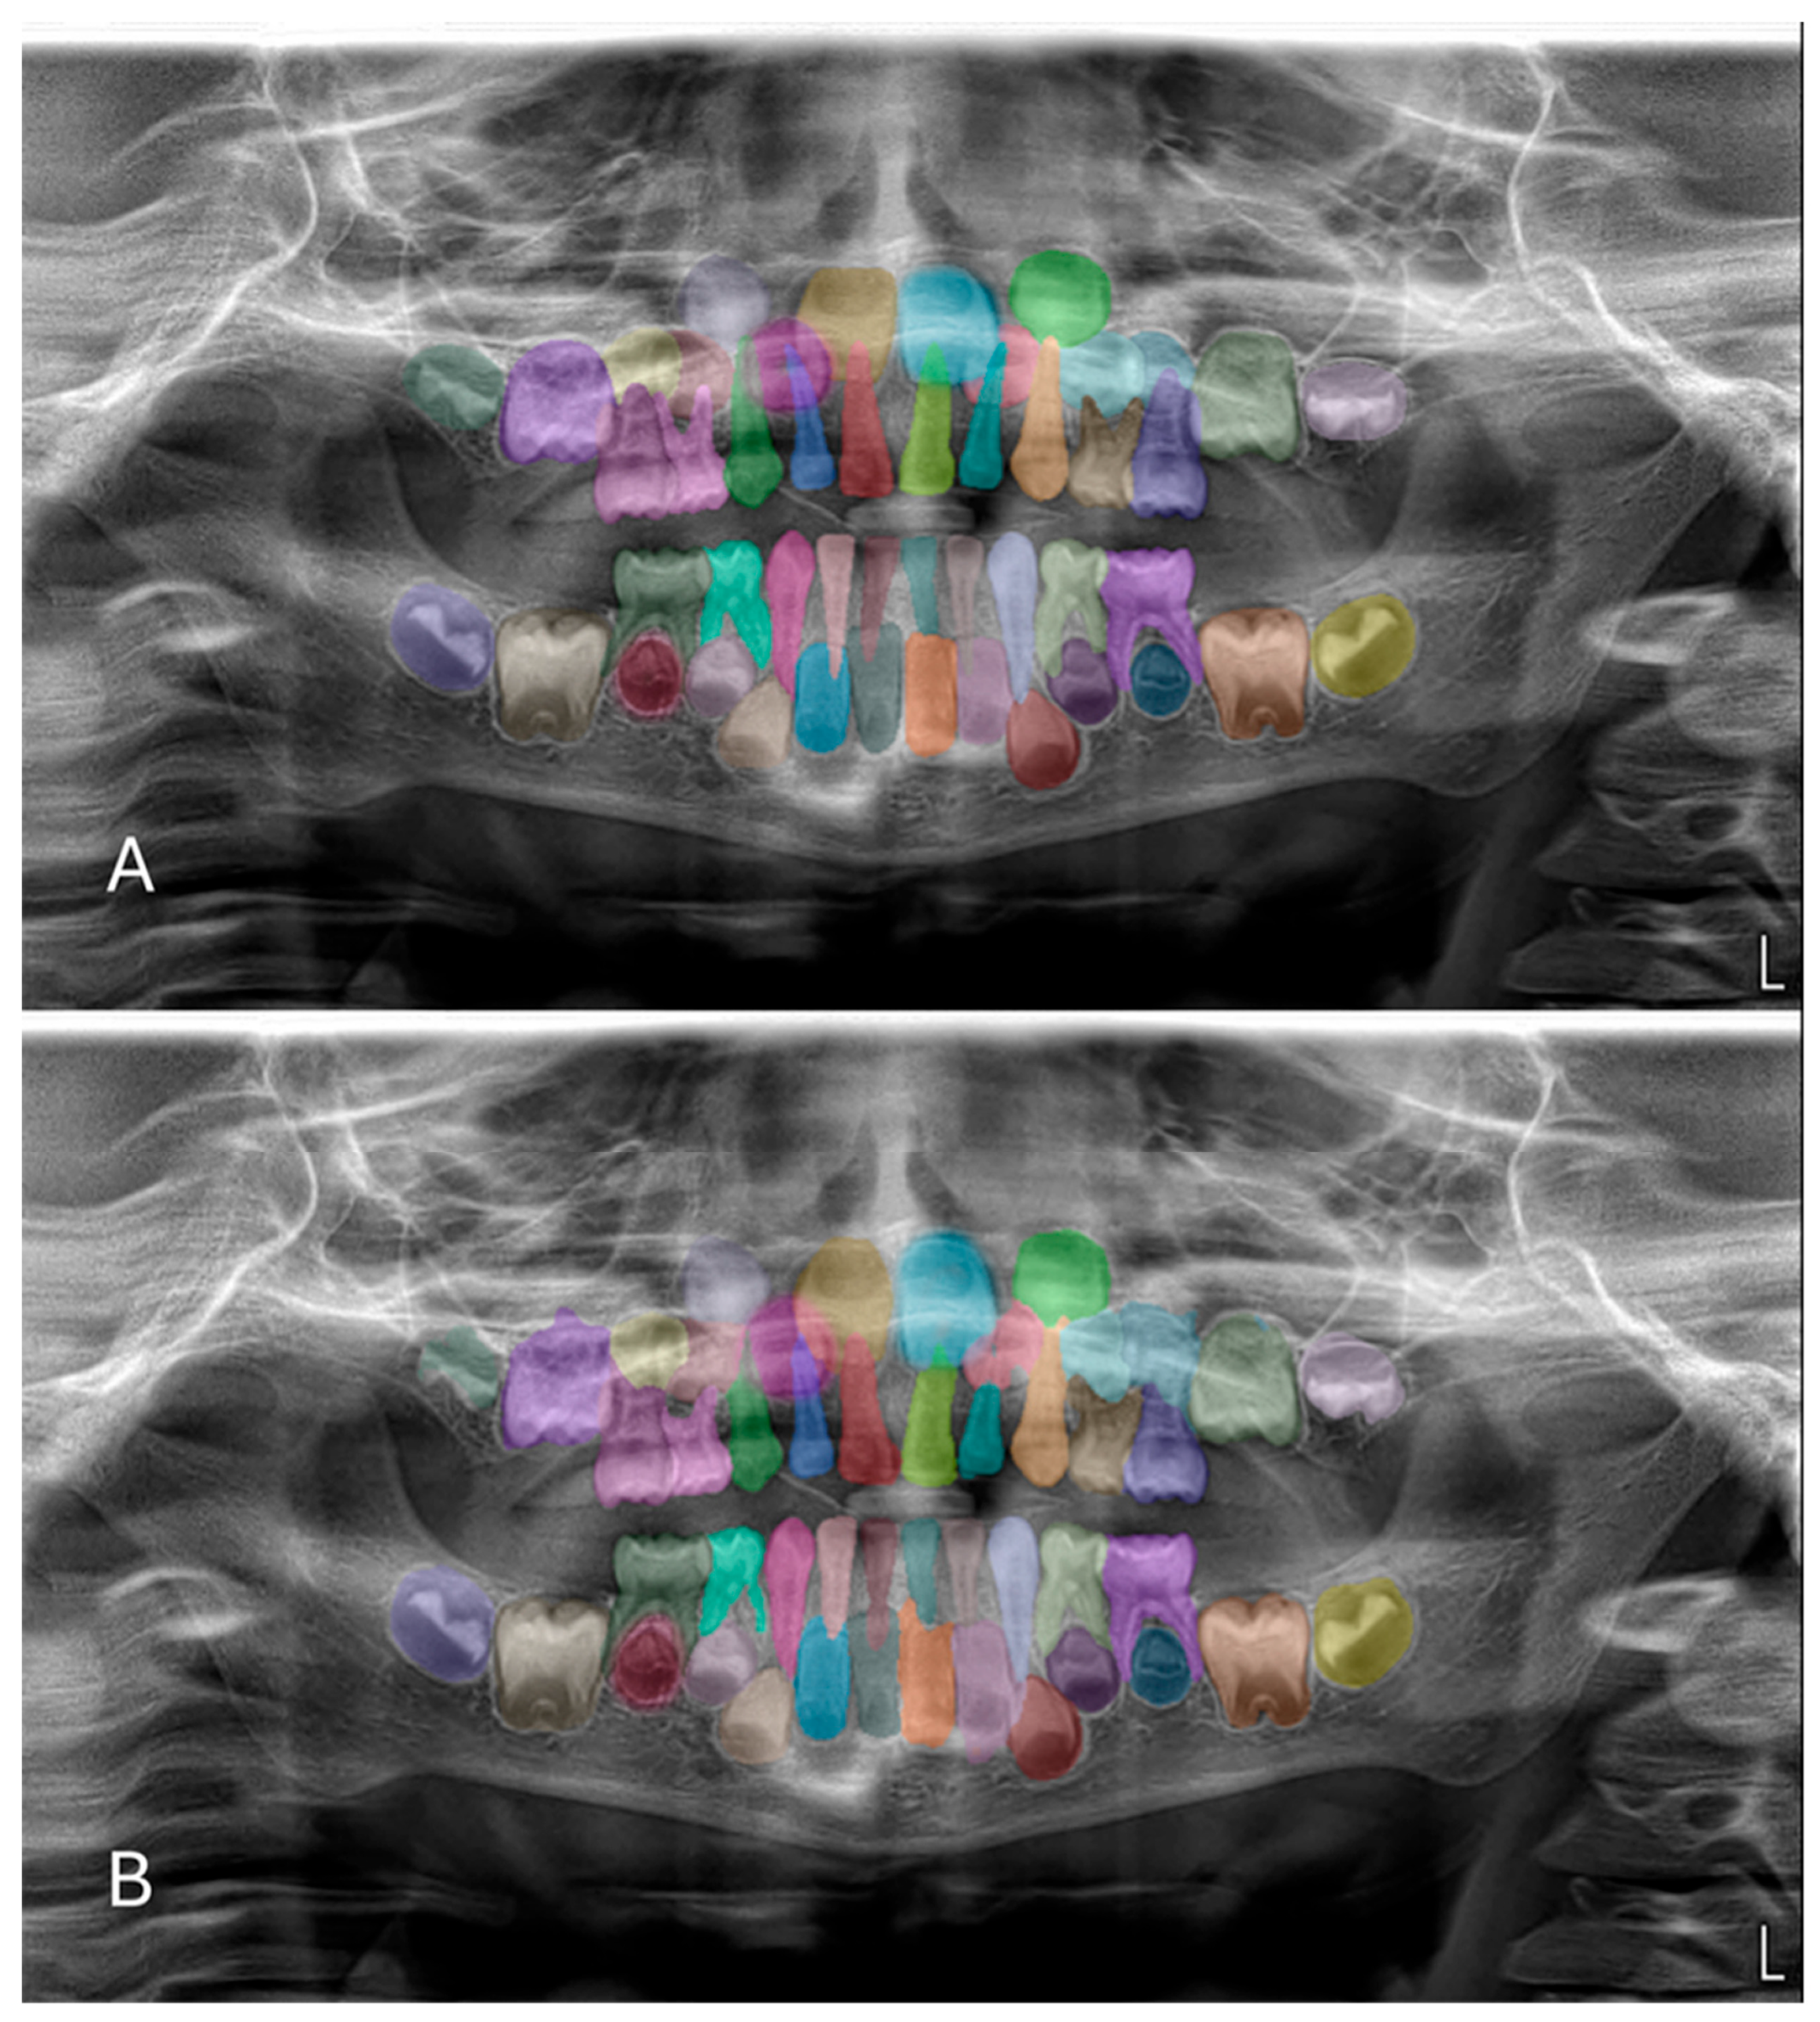

In the test phase, the U-Net-based deep learning model demonstrated robust segmentation and classification performance of primary and permanent teeth in panoramic radiographs. The Dice similarity coefficient (DSC) was 0.8773, indicating a substantial overlap between the model’s predicted segmentations and the ground-truth annotations (Figure 2 and Figure 3). Concurrently, the intersection over union (IoU) score of 0.8125 reflected the model’s ability to precisely localize target structures. Further supporting its robustness, the model achieved a precision of 0.9115 and a recall of 0.8974, leading to an F1 score of 0.9027. Collectively, these metrics confirm the model’s capacity to accurately delineate teeth while maintaining a balanced trade-off between false positives and false negatives. During the validation phase, the model maintained a high accuracy of 96.71%, indicating consistent performance across a variety of panoramic radiographs. Although the validation DSC (0.8062) and IoU (0.6936) were slightly lower than the test phase metrics—possibly due to dataset variability—the values remained indicative of reliable segmentation. Additionally, the validation loss was recorded at 0.2571, which falls within an acceptable error range for this type of segmentation task. Notably, the peak validation DSC reached 0.8540, while the highest IoU was 0.7556, suggesting that the model shows potential for further refinement.

Figure 3. Example images demonstrating the performance for segmentation of mixed dentition on panoramic radiographs between manual annotation by researchers and U-Net based artificial intelligence (AI)-predicted label masks. (A) Manual segmentation performed by clinicians. (B) Automatic segmentation by the model. In the segmentation figures, each tooth is represented with a distinct colour to visually differentiate regions; however, the model treated all teeth as unified segmentation classes during training.